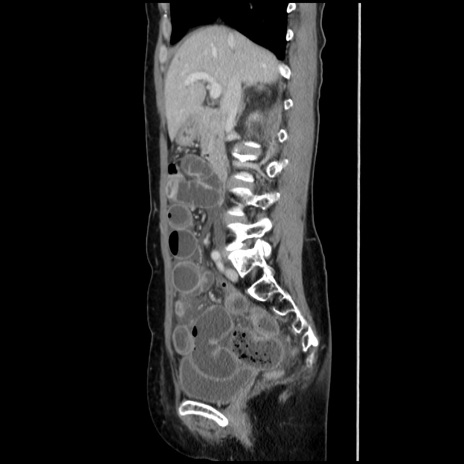

横断像

【症例】40歳代 女性

【主訴】上腹部痛、嘔気・嘔吐

【現病歴】約9時間前頃から急に上腹部痛、嘔気、嘔吐が出現。改善しないため救急要請。

【既往歴】子宮頚癌(広汎子宮全摘術、放射線療法)、腸閉塞

【身体所見】腹部:平坦、軟、腸雑音亢進、上腹部を中心に腹部全体に圧痛あり。

【データ】WBC 8400、CRP 0.03